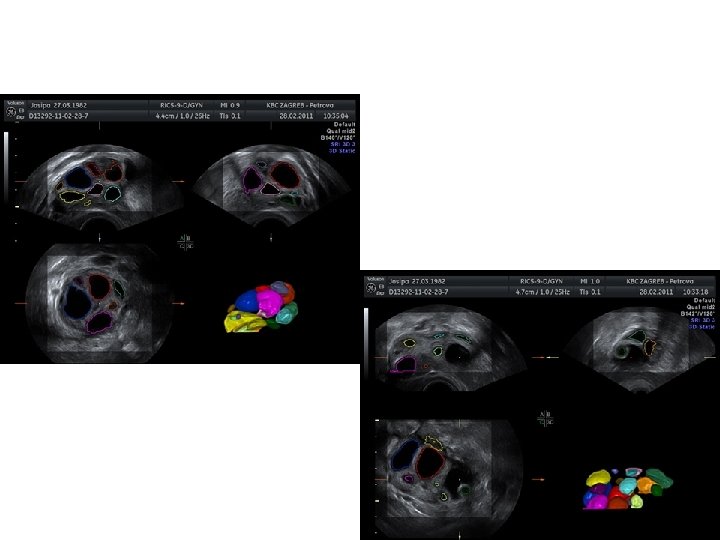

3 D UZV - VOLUMEN JAJNIKA • 2 osnovne metode za izračun volumena: Konvencionalna „multi planar” metoda VOCAL (virtual organ computer-aided analysis)

3 D UZV – BROJ FOLIKULA • Antral follicul count

PROCJENA PROTOKA KRVI • 3 D PD omogućuje procjenu vaskularizacijele ovarijske strome • Rezultat se prikazuje kao histogram (VI, FI, VFI) • Kontradiktorni rezultati (Pan et al, Lam et al, Jarvela et al, Ng et al)

STROMA • Analiza 3 D volumena - prosječan intenzitet voxela u volumenu – MEAN GRAYNESS • Battaglia et al, 2012. . ehogenost strome je značajno povišena u pacijentica s PCOS tipičan UZV oznaka PCOS

STROMA • Volumen strome je značajno povišen kod žena s PCOS – hipoteza o vjerojatnom izvoru hiperprodukcije androgena u teka stanicama • V strome= V jajnika – ukupni V folikula • Omjer V strome/ V jajnika > 0. 84 – odličan prediktor hiperandrogenemije i hirzutizma (Battaglia et al, 2012. )